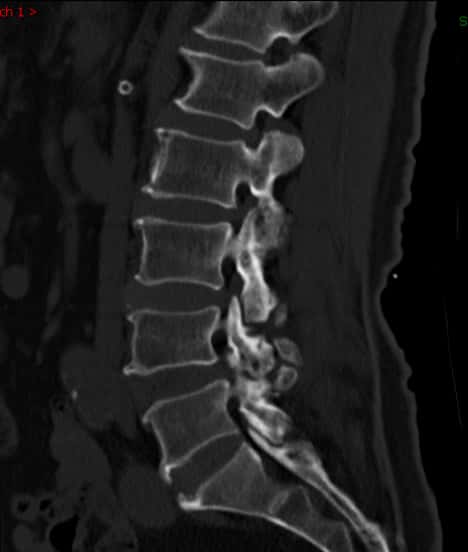

腰椎正位片腰椎退变增生,其他问题并不严重。

腰椎正位片子看腰椎退变增生,其他问题并不严重。

腰椎侧位片子看腰4/5有轻度滑脱。